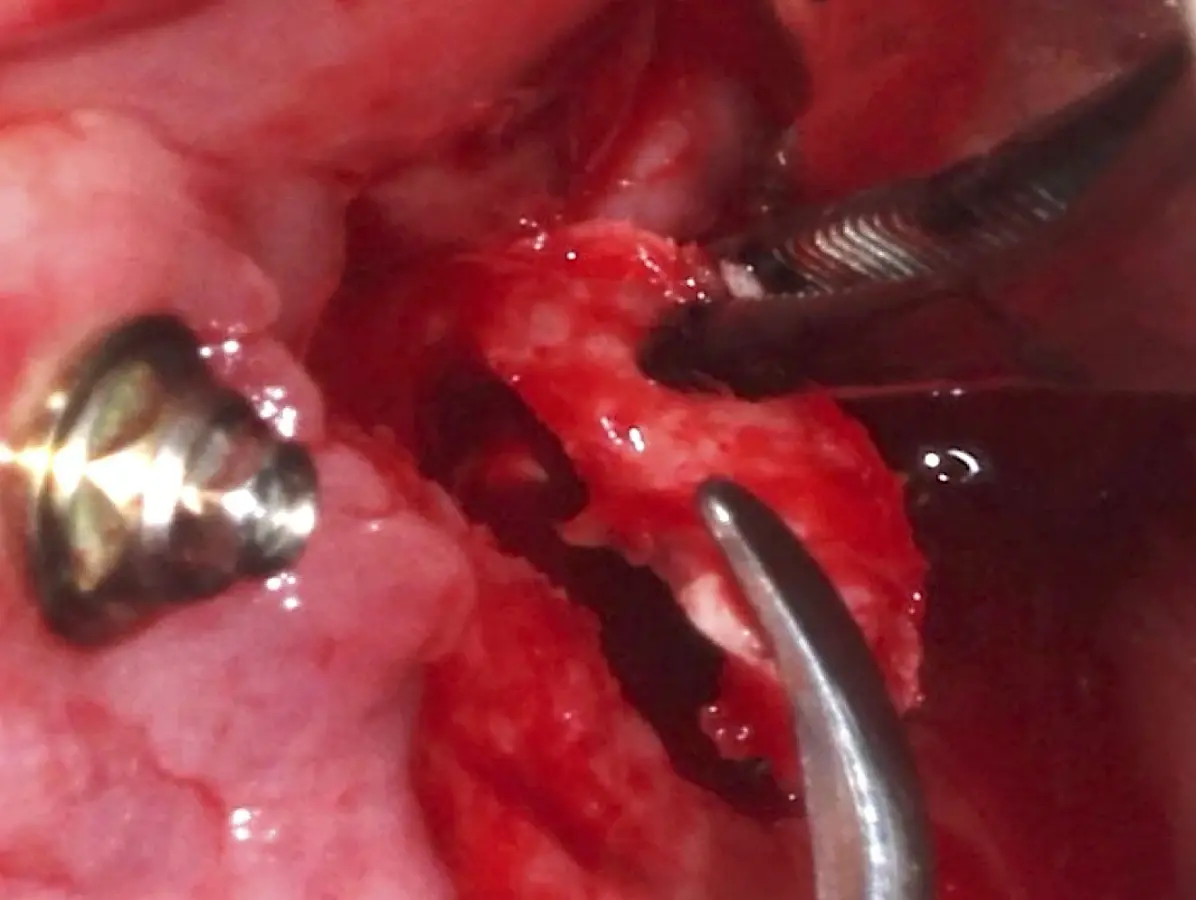

La técnica se inicia con la colocación de anestesia infiltrativa, posteriormente se realiza una incisión crestal o paracrestal con posibles liberantes verticales que deben de estar alejadas por lo menos 5 mm de los límites de la futura ventana y sobrepasar la línea mucogingival. Se realiza una elevación de colgajo, se inicia la antrostomía y antroplastía. Para ello, se emplea el inserto redondo diamantado de corte al momento de delimitar los bordes de la ventana de acceso. Luego se cambia al inserto aserrado liso de calibre fino con superficie diamantada, para profundizar y eliminar el hueso en el contorno de la ventana. Una vez que se traslucen los tejidos, se puede optar por el retiro de la tapa ósea o el levantamiento de ésta junto con la membrana.

El tipo de inserto a ser utilizado dependerá del espesor de la pared ósea. Si la pared es menor a 0.5 mm, es mejor utilizar insertos de desgaste para prevenir la ruptura de la membrana de Schneider; si el espesor es mayor a 0.5 mm, se puede utilizar insertos de corte de espesor medio (Figura 3).